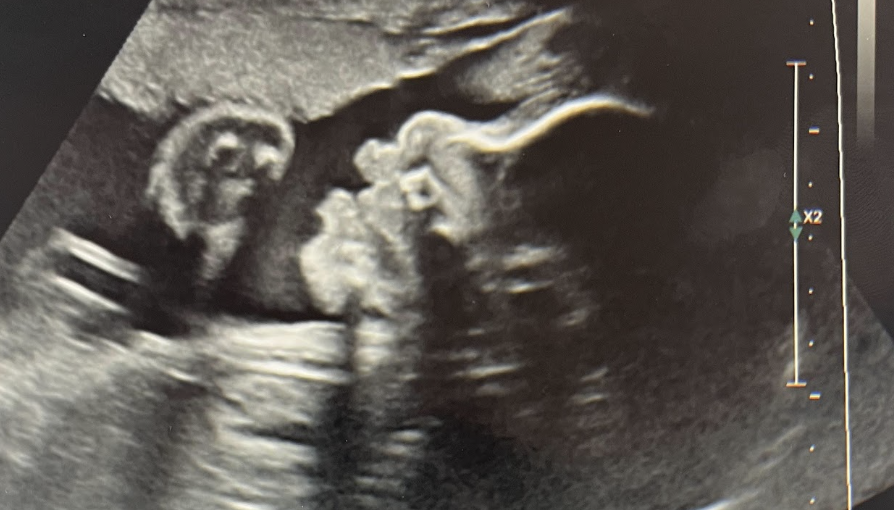

25 Weeks Gestation

Renee was prenatally diagnosed with hypoplastic left heart syndrome, double outlet right ventricle, and malposed great arteries at 25 weeks and 2 days.